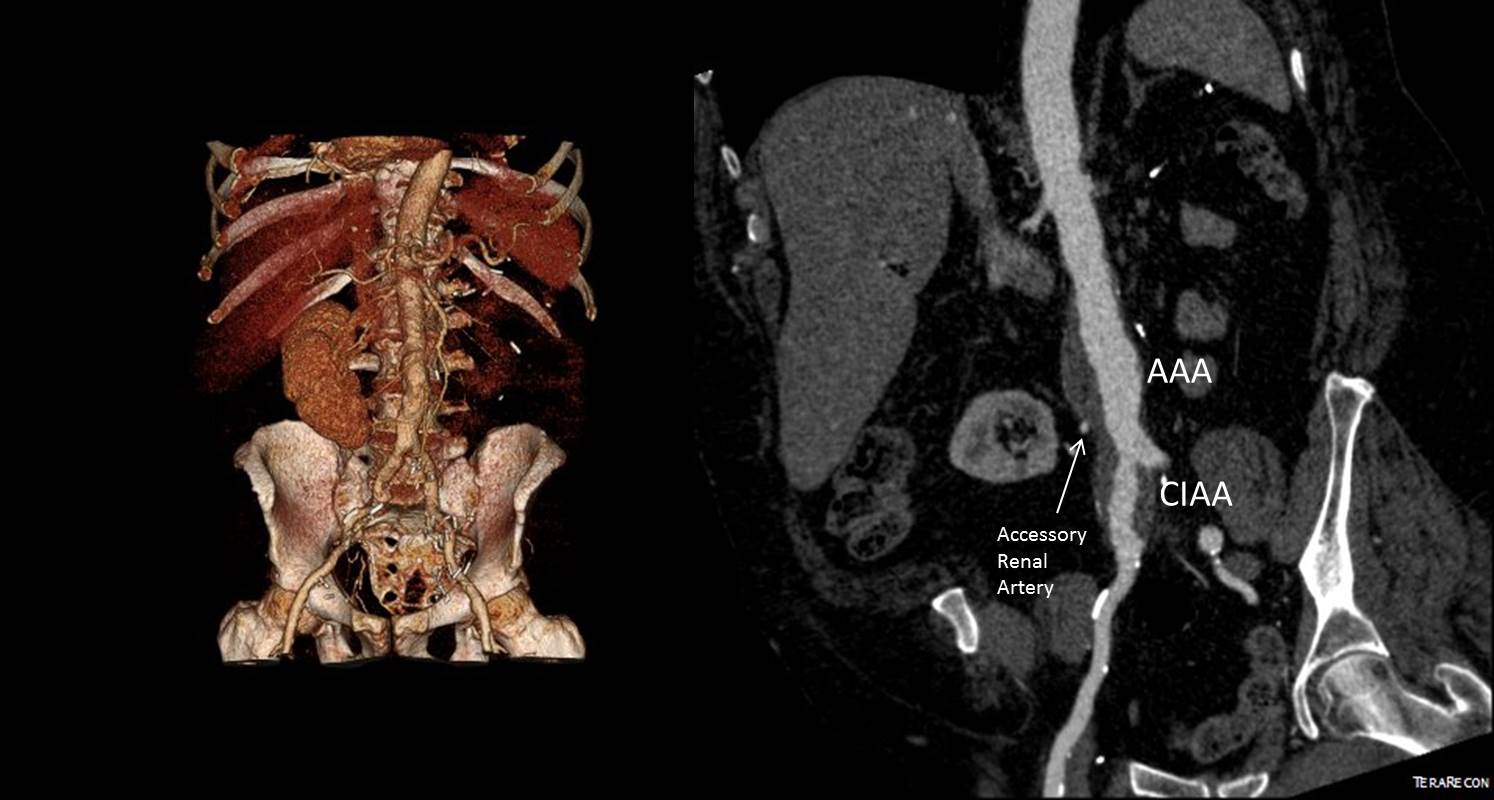

A Troublesome Accessory Renal Artery Complicating a Complicated Patient

Preop Figure

The patient is an 65 year old man with a growing right common iliac artery aneurysm of 3.7cm, a small AAA, and severe COPD (not oxygen dependent, FEV 1.5L) . He had a prior left nephrectomy for cancer as well as a bladder resection and prostatectomy with an ileal conduit (Indiana pouch or neobladder), with complex abdominal wall closure complicated by infection of Marlex in the past, and prior operations for small bowel obstruction. He is morbidly obese. His kidney function was stable with a Cr 1.5dL/mL, calculated GFR or 44mL/min. His nuclear cardiac stress test (pharmacologic) was normal.

A magnified view of the accessory renal artery is shows below with the arrow

mag preop CT

He needed to have his right CIAA treated but the issues were what to do with his accessory renal artery. Vascular surgery is all about making the right decisions with fall back plans. As with most complicated patients, the options are numerous.

I informally polled my partners and found an absence of consensus except for rejecting #1, 2, and 7. The first two options were not optimal because of his prior operation and because of the location of his disease. The third option had its proponents, but I felt that the kidney and pouch were in jeopardy from dissection in that area. The open debranching had its appeal for others, but for the same reasons that I rejected #3, I rejected #4 –potential harm to the kidney. #5 may be an option, but in my experience, I have seen too many patients referred for failure of parallel grafts to feel secure about offering it.  #6 would be reasonable if the patient could avoid dialysis. With a calculated CGF of 44ml/min, losing half the remaining kidney would barely leave him off dialysis. By appearances though, the smart money was on losing less than 50% but more than 20%. A 30% loss would result in a GFR of 30mL/min or a Cr of 2.1 which made dialysis not likely. In my experience, the kidney does have some collateralization as evidenced by backbleeding of accessory renals with an infrarenal clamp so it may be that he might lose only 10-15%. I discussed all of these options and medical management with the patient who agreed to proceed with option 5 under my recommendation. My plan was to assess the flow from the accessory renal and proceed if it was small, with plan B being a parallel graft, plan C debranching.

nephrogram

In the OR, the right accessory renal artery was selectively catheterized and a nephrogram revealed that it supplied less than 20% of the kidney. The above diagram shows the extent of the total kidney and the area perfused by the accessory renal artery. I proceeded with coil embolization of it and the right hypogastric artery and EVAR of the AAA/R.CIAA.

post CT

In followup, the patient had a Cr of 1.7mg/dL, representing about 15% loss of kidney function. As the case was done percutaneously, he only had 1cm incision in both groins, and was pleased with his result. No endoleak was seen (CT above).